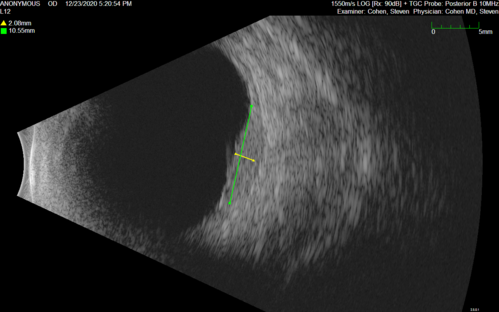

51 year old female.  First 3 sets of images show lesions growing despite systemic chemotherapy.  She eventually had external beam radiation x 15 sessions and the tumors shrunk in the last two sets of images